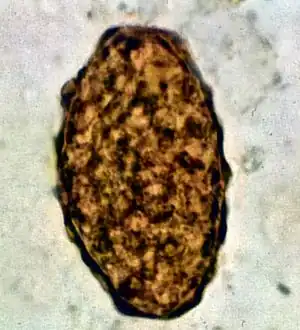

Fertile egg as can be seen in a microscope

Fertile egg in human faeces (detail)

Ascaris lumbricoides is characterized by its great size. Males are 2–4 mm (0.08–0.2 in) in diameter and 15–31 cm (5.9–12 in) long. The male's posterior end is curved ventrally and has a bluntly pointed tail. Females are 3–6 mm (0.1–0.2 in) wide and 20–49 cm (7.9–19 in) long. The vulva is located in the anterior end and accounts for about one-third of its body length. Uteri may contain up to 27 million eggs at a time, with 200,000 being laid per day. Fertilized eggs are oval to round in shape and are 45–75 μm (0.0018–0.0030 in) long and 35–50 μm (0.0014–0.0020 in) wide with a thick outer shell. Unfertilized eggs measure 88–94 μm (0.0035–0.0037 in) long and 44 μm (0.0017 in) wide.[9]